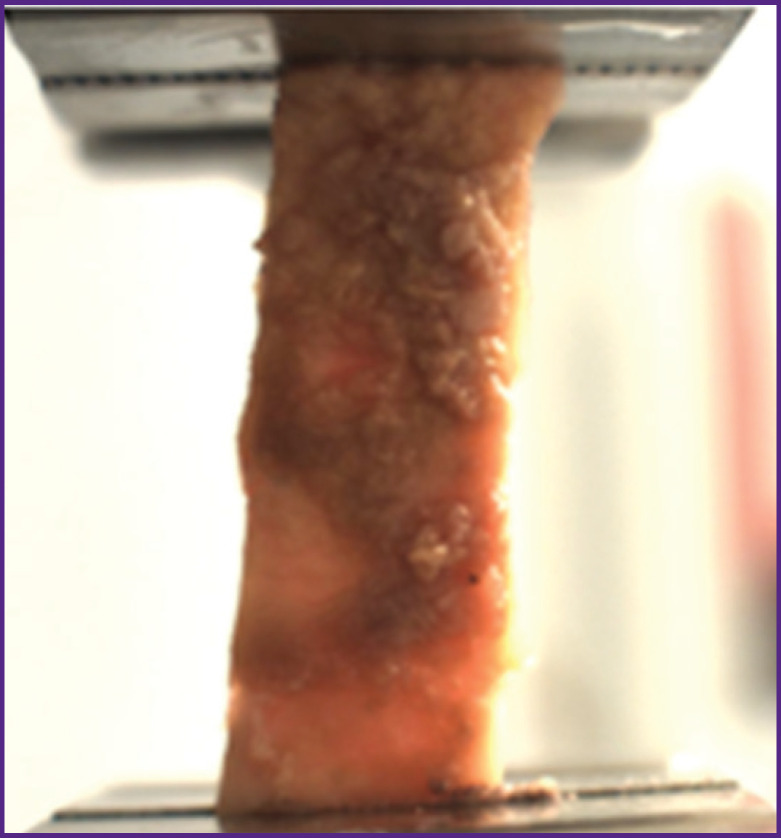

Materials and methods: The study experimental material was the resected parts of the aortic aneurysm obtained during aneurysm replacement surgery in a patient with uncontrolled arterial hypertension. The direct mechanical testing methods such as instrumental indentation and uniaxial extension were used.

Results: It was shown that by the direct instrumental indentation it is possible to accurately assess and compare the stiffness of all three layers of the aortic wall. In this clinical case, the inner aorta layer was subject to the greatest atherosclerotic damage. In the media area, the values of this indicator were widely scattered, whereas the material was greatly dissected. By uniaxial extension method it is possible to obtain accurate parameters of the vascular wall strength, as well as to assess the stiffness, elasticity, and deformability of the intraoperatively resected aortic tissue. It was found that the aneurysm aortic wall, compared with the non-dilated aortic section, was characterized by a significantly lower strength in both longitudinal (by 4.25 times) and transverse (by 3.75 times) directions. In addition, aneurysm tissues demonstrated a significantly lower elasticity and deformability.